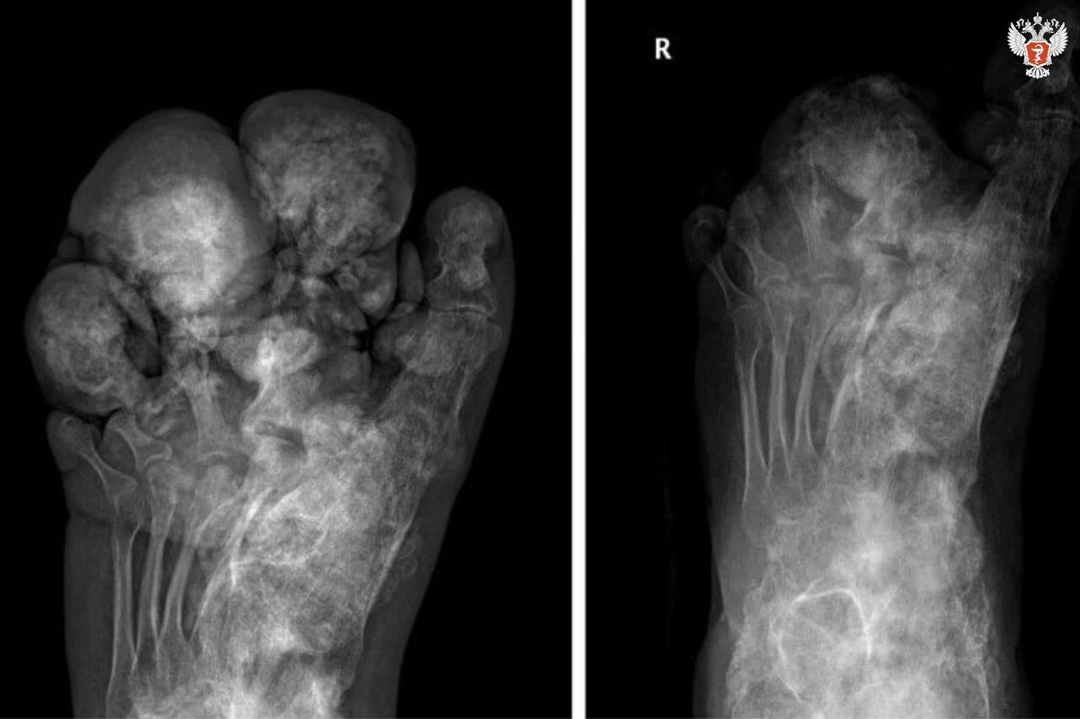

➡️ Из-за этой патологии правая нога молодого человека была сильно деформирована и увеличена в объеме.

Со временем на правой ноге начали образовываться патологические костные наросты — от стопы до бедра, которые причиняли сильные боли.

Специалисты медучреждения сформировали функциональную стопу, удалили костные разрастания и выполнили замыкание голеностопного сустава, который находился в порочном положении.

1⃣ Во время операции специалисты удалили объемные костные наросты и сформировали стопу, близкую к анатомически правильной форме.